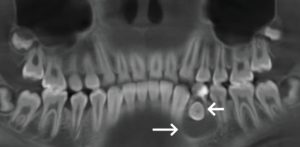

Tratamiento de un premolar impactado con dilaceración radicular causada por un quiste radicular en un molar deciduo

Para comenzar la semana les traemos un artículo llamado Management of Impacted Premolar With Root Dilaceration Caused by Radicular Cyst in Deciduous Molar: A Case Report, publicado en el Case Reports in Dentistry. Este reporte trata sobre un caso clínico en el que un niño de 11 años tenía un quiste radicular en un diente … Sigue leyendo Tratamiento de un premolar impactado con dilaceración radicular causada por un quiste radicular en un molar deciduo